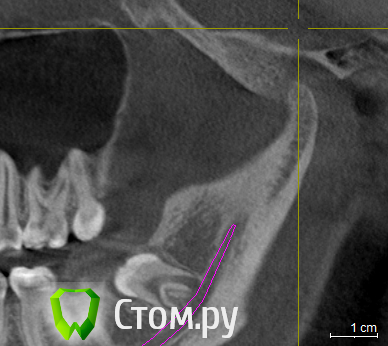

ElenaV Опубликовано 29 июня, 2014 Поделиться Опубликовано 29 июня, 2014 (изменено) Здравствуйте, дорогие доктора! У моей дочери 16ти лет проблема с ВНЧС. При ношении брекетов ей вытягивали нижнюю челюсть, выравнивали прикус и зубы , в частности - клыки выпирающие выравнивали. А через 1,5 года после снятия в одно прекрасное утро не смогла открыть рот. Нам советовали делать лазер, становилось легче. Так было 2 раза. А теперь по утрам, если спит на правой щеке, то челюсть правую заклинивает. Голова сильно болит в висках. Связано ли это с брекетами или другая причина может быть? У нас в Красноярске мы нашли доктора, который собрался нам помочь, поставить шины http://astreja.ru/uslugi/neyro-myshechnaya-stomatologiya. Может ли шина помочь решить эту проблему? В Красноярске выбор докторов небольшой, можно сказать - его нет. И уже просто страшно становится. Читая в интернете об этой проблеме, поняла, что это дело очень тонкое и непростое, испортить жизнь ребенку можно запросто. А еще советуют мануального терапевта. Куда пойти ? Может ли мануальный терапевт решить эти проблемы? Знакомый стоматолог сказал, что если челюсть поправят, то прикус может нарушится. А мануальный говорит - приходите - все исправим, даже снимков ему не надо. Теперь хочу выяснить у специалистов, как все таки поступить. К кому пойти сначала. Очень Вам буду благодарна за совет.Дорогие доктора, можете подсказать, что с суставом? Доктор сказал, что сустав находится далеко от височной кости, т.е. расстояние больше чем норма. Напишите, пожалуйста, что Вы видите на снимке, какую патологию. Вот еще сделала скриншоты суставов: левый и правый Вот еще правый сустав, немножко по другому Изменено 29 июня, 2014 пользователем ElenaV Ссылка на комментарий

Skip Опубликовано 29 июня, 2014 Поделиться Опубликовано 29 июня, 2014 Напишите, пожалуйста, что Вы видите на снимке, какую патологию. Эти КТ, с полуоткрытым ртом и выдвинутой челюстью, мало о чём говорят. У вас там что, уже стоит шина? Ссылка на комментарий

ElenaV Опубликовано 30 июня, 2014 Автор Поделиться Опубликовано 30 июня, 2014 (изменено) Эти КТ, с полуоткрытым ртом и выдвинутой челюстью, мало о чём говорят. У вас там что, уже стоит шина?Шины еще нет, мы сходили на прием, советуют ставить шину. Это КТ в 3Д делали с пластиной во рту, сказали - так надо. Что обычно так делают.Может поэтому и кажется доктору, что сустав неправильно в лунке стоит? Доктор сказал, что сустав далеко стоит от нормального местоположения. Поэтому выскакивает.Нужно МРТ сделать что бы точно понять? Или КТ переделывать? Изменено 30 июня, 2014 пользователем ElenaV Ссылка на комментарий

Force Опубликовано 1 июля, 2014 Поделиться Опубликовано 1 июля, 2014 с восковым шаблоном это по Маклафлину в ЦС сделано КТ. 1 Ссылка на комментарий

ElenaV Опубликовано 1 июля, 2014 Автор Поделиться Опубликовано 1 июля, 2014 с восковым шаблоном это по Маклафлину в ЦС сделано КТ. А как понять по этому КТ, правильно ли стоит сустав? Если рот открытый на снимке? Ссылка на комментарий

Skip Опубликовано 1 июля, 2014 Поделиться Опубликовано 1 июля, 2014 с восковым шаблоном это по Маклафлину в ЦС сделано КТ. Понятно. Ну тогда и с привычной окклюзией стоило бы сравнить, т.е. два снимка, а вернее три, если добавить макс. открытие рта. 1 Ссылка на комментарий